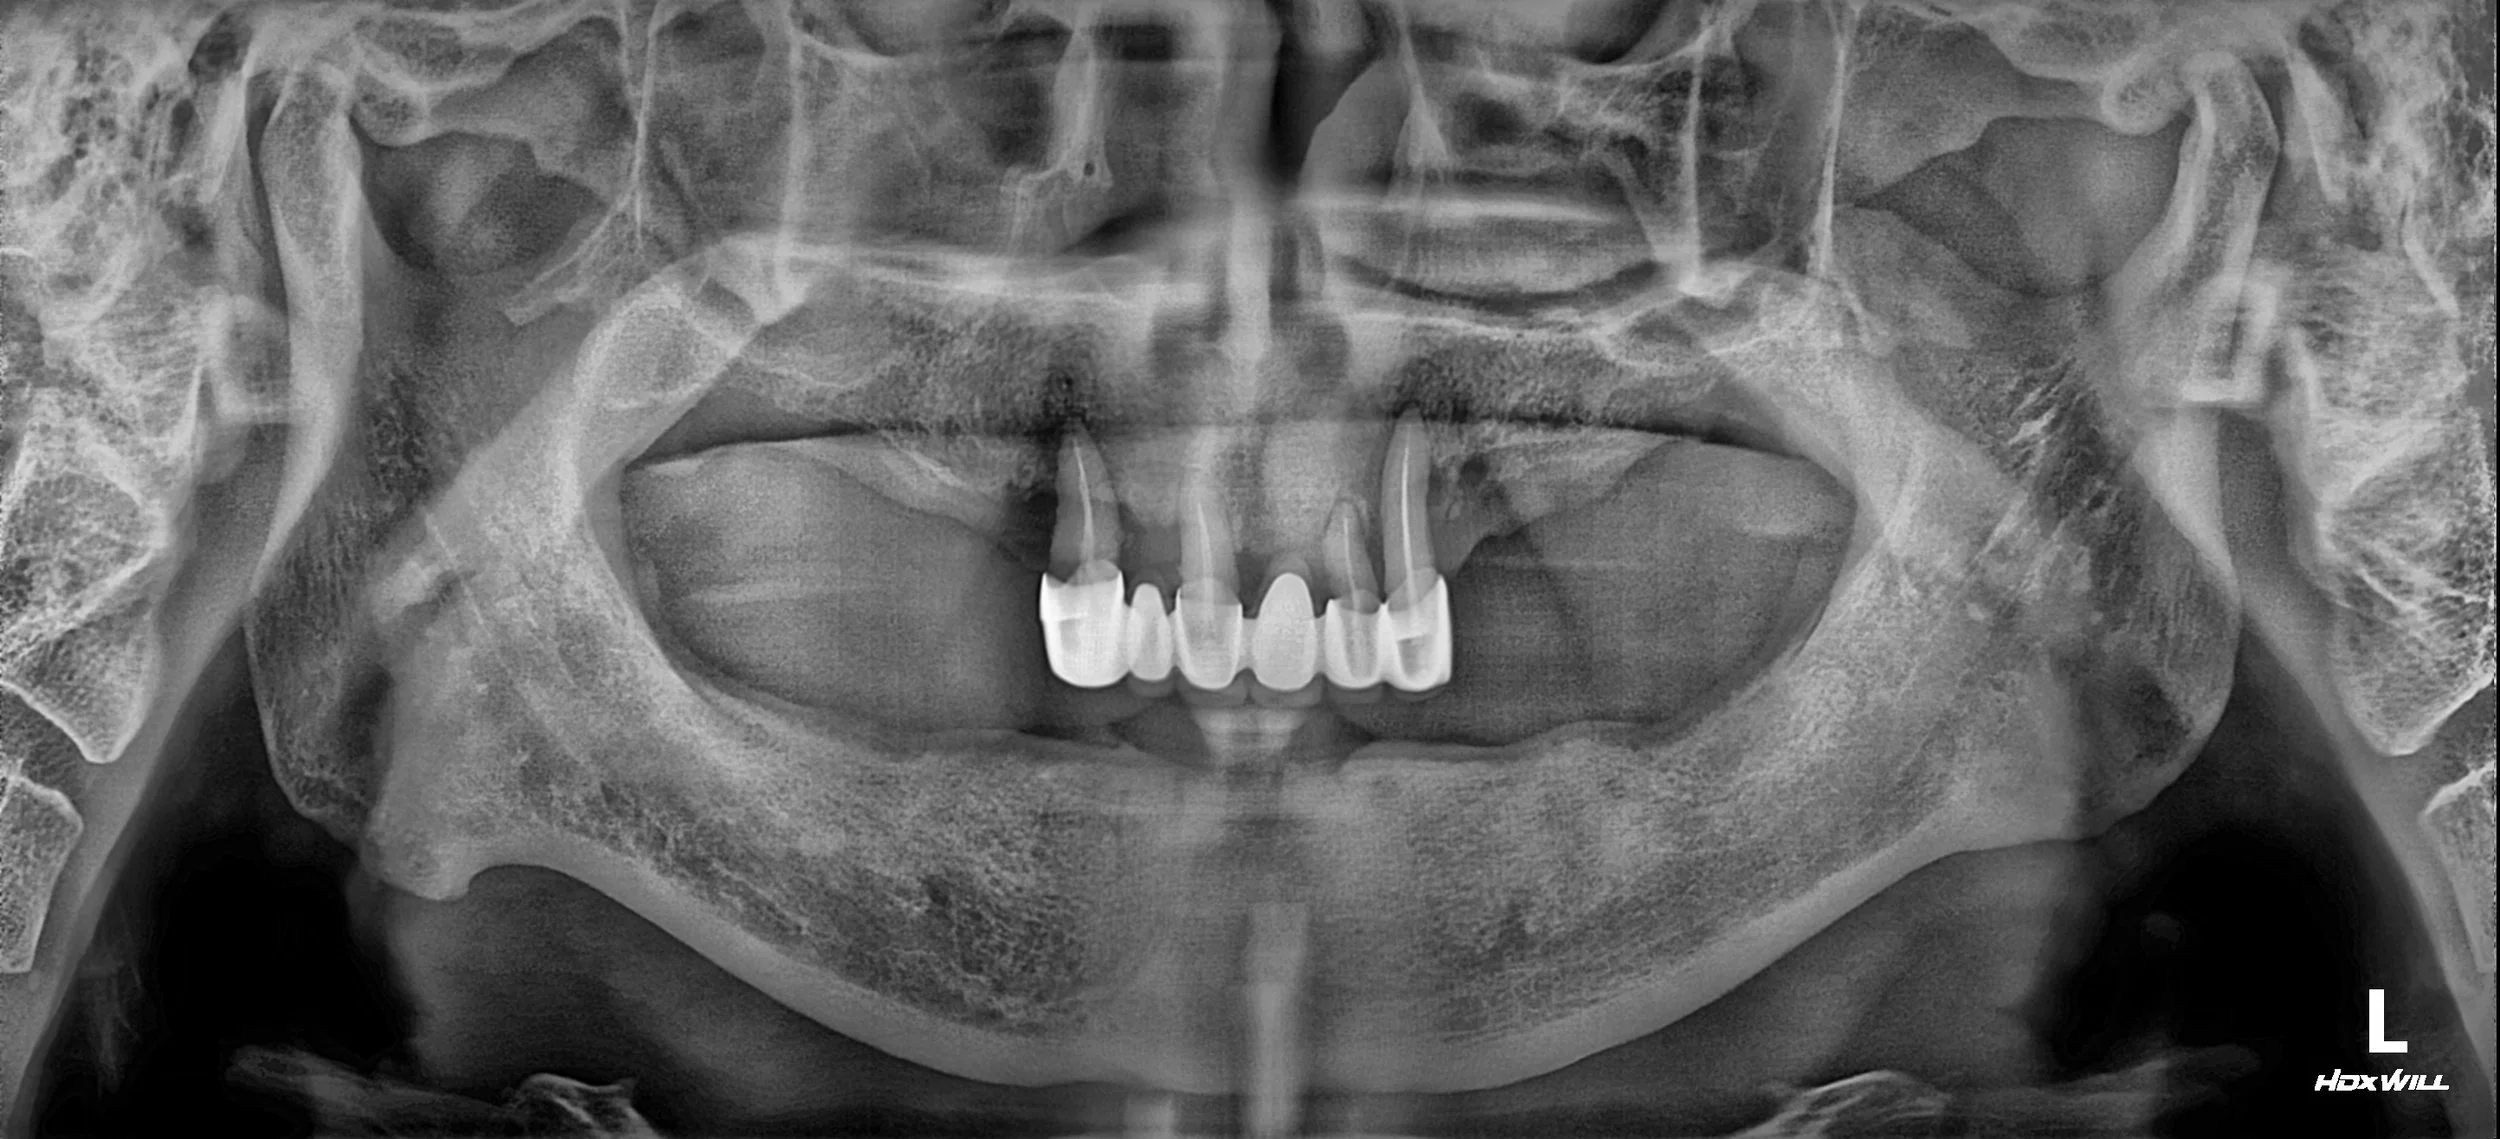

OPG - BEFORE

• Long-term Denture Wear: Years of relying on removable partial dentures had led to progressive disuse atrophy of the periodontal tissues and underlying alveolar bone.

• Failing Anterior Bridge: A pre-existing maxillary anterior bridge had failed, causing localized but severe vertical and horizontal bone loss in the aesthetic zone.

• Complete Occlusal Failure: With no stable posterior stops and a failing anterior segment, the patient's masticatory efficiency was nearly non-existent.